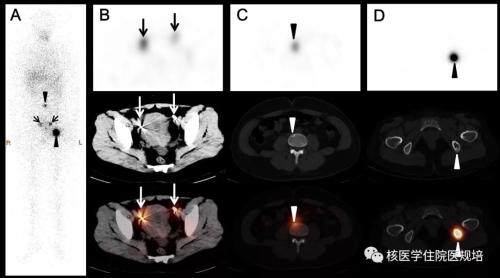

图1.131I全身前后位平面显像

图2 盆腔SPECT/CT显像

口服131I5.55 GBq后3天行全身显像(图1),结果见:颈部甲状腺区域未见明显异常示踪剂浓集区;口鼻部及胃肠道可见生理性示踪剂摄取;盆腔内膀胱左上方可见一团片状不规则异常示踪剂浓集区,进一步行相应区域SPECT/CT后,见该浓聚灶位于乙状结肠,CT可见一由肠腔向外突出的囊袋影(图2)。全身其他部位未见明显异常显像剂摄取。

1.颈部未见明显残留甲状腺组织显影,符合清甲治疗后改变

2.全身未见明显功能性转移性病灶

3.盆腔内131I浓聚灶考虑位乙状结肠憩室内滞留可能性大,建议进一步肠镜检查。

本例女性患者,既往否认肠道疾病史,否认子宫肌瘤等妇科疾病史,围碘治疗期无便秘、腹痛等症状。该患者刺激性Tg并不达标,且首次治疗后刺激性Tg水平降低,131I Rx-WBS显示盆腔团块状异常示踪剂浓集区,并不能除外有功能性转移灶存在。因此临床并不能完全用生理性或异位摄取原因解释,进一步行腹部及盆部断层显像也是非常有必要的。盆腔断层显像显示乙状结肠憩室放射性滞留,放射性碘治疗后1月行肠镜检查证实为乙状结肠憩室,排除盆腔功能性转移性病灶,对患者诊断分期、治疗评价及后续治疗方案的确定有决定性意义。